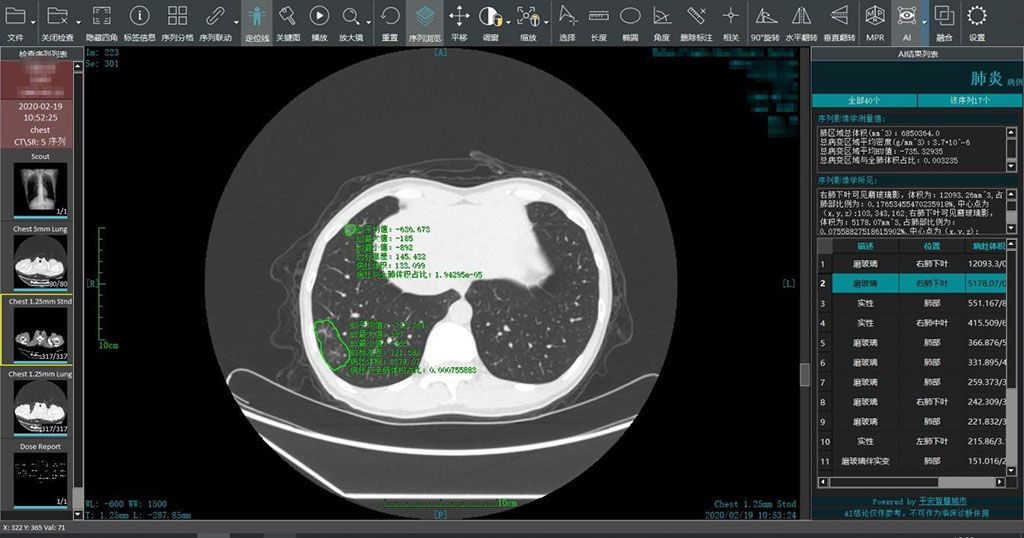

El sistema inteligente de lectura de imágenes COVID-19 de Ping An Smart Healthcare (SHENZHEN, China) utiliza un motor de IA para realizar un análisis comparativo de imágenes múltiples de tomografías computarizadas (TC) del mismo paciente para medir los cambios en las lesiones El sistema inteligente de lectura de imágenes de IA también admite imágenes remotas realizadas por profesionales médicos fuera de las áreas epidémicas, lo que ayuda a rastrear el desarrollo de la enfermedad. Las instituciones médicas que requieren servicios inteligentes de lectura de imágenes COVID-19 pueden obtener acceso en plataformas de nube públicas o privadas o en las instalaciones.

Imagen: Un sistema inteligente de lectura de imágenes genera análisis rápidos en áreas epidémicas (Fotografía cortesía de Ping An Smart Healthcare)

Ping An Smart Healthcare pone el software a disposición de casi 800 millones de personas en más de 70 ciudades de China y el sudeste asiático afiliadas a la compañía. El sistema inteligente de lectura de imágenes también se puede adaptar rápidamente para trabajar directamente con equipos de TC (con la ayuda de los fabricantes) para ayudar a diagnosticar el brote de COVID-19. A nivel individual, se puede usar para evaluar el tratamiento y el pronóstico de pacientes infectados, ayudando a los médicos a diagnosticar, clasificar y evaluar a los pacientes con COVID-19 de manera rápida y efectiva.

“Desde su lanzamiento, el sistema inteligente de lectura de imágenes ha brindado servicios a más de 1.500 instituciones médicas. Más de 5.000 pacientes recibieron servicios inteligentes de lectura de imágenes de forma gratuita. El sistema puede generar resultados de análisis inteligentes en alrededor de 15 segundos, con una tasa de exactitud superior al 90%”, dijo Geoff Kau, copresidente y director de estrategia de Ping An Smart City”. En comparación, a los radiólogos les toma alrededor de 15 minutos leer las imágenes de TC de un paciente sospechoso de contraer el COVID-19”.